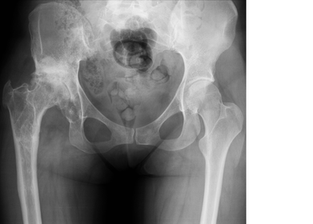

ЕНДОПРОТЕЗИРАНЕ ТАЗОБЕДРЕНА СТАВА

Пациент 4